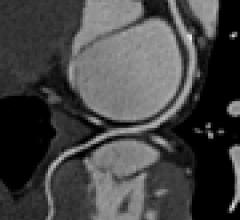

Feature | Computed Tomography (CT) | Dave Fornell

(More recent articles and videos on trends, advances and innovations in computed tomography systems can be found at the…

Over the past few years, iterative reconstruction has emerged as an alternative to filtered back projection with its…